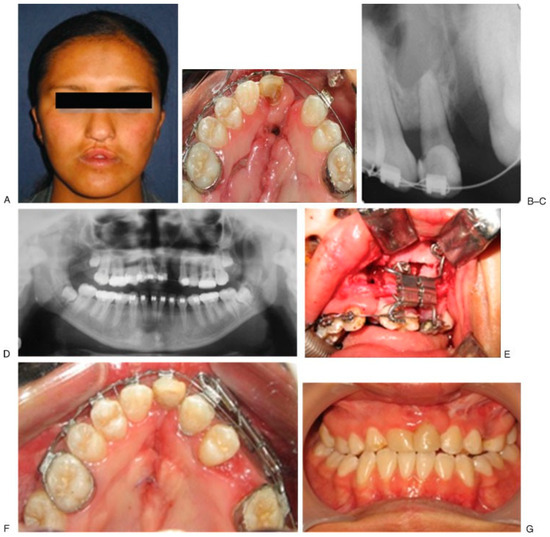

- Case 1 was a 17-year-old male patient with cleft lip and palate, right-unilateral, treated with ABT bifocal (Figure 3).

Figure 3. Initial aspect (A–E). Design of the device (F). End bifocal alveolar bone transportation technique (G). Closing of alveolar fistula at 57 weeks of follow-up (H–J). Regenerated new bone behind of the used transport disk (K). - Case 2 was a 16-year-old female patient with sequel of cleft lip and palate and active oronasal fistula, treated with bifocal ABT (Figure 4).